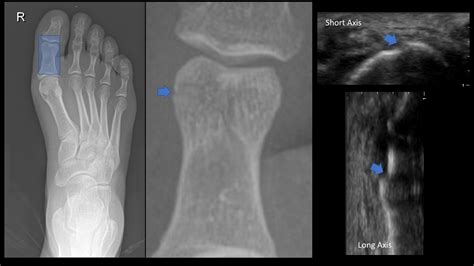

Diagnosing a Proximal Phalanx Fracture typically involves a combination of physical examination and imaging tests. The diagnostic process may include:

• X-rays: Imaging tests to visualize the bone and determine the extent and location of the fracture.

• CT Scans or MRIs: In some cases, more detailed imaging may be required to assess the fracture and surrounding tissues.

• proximal phalanx fracture toe